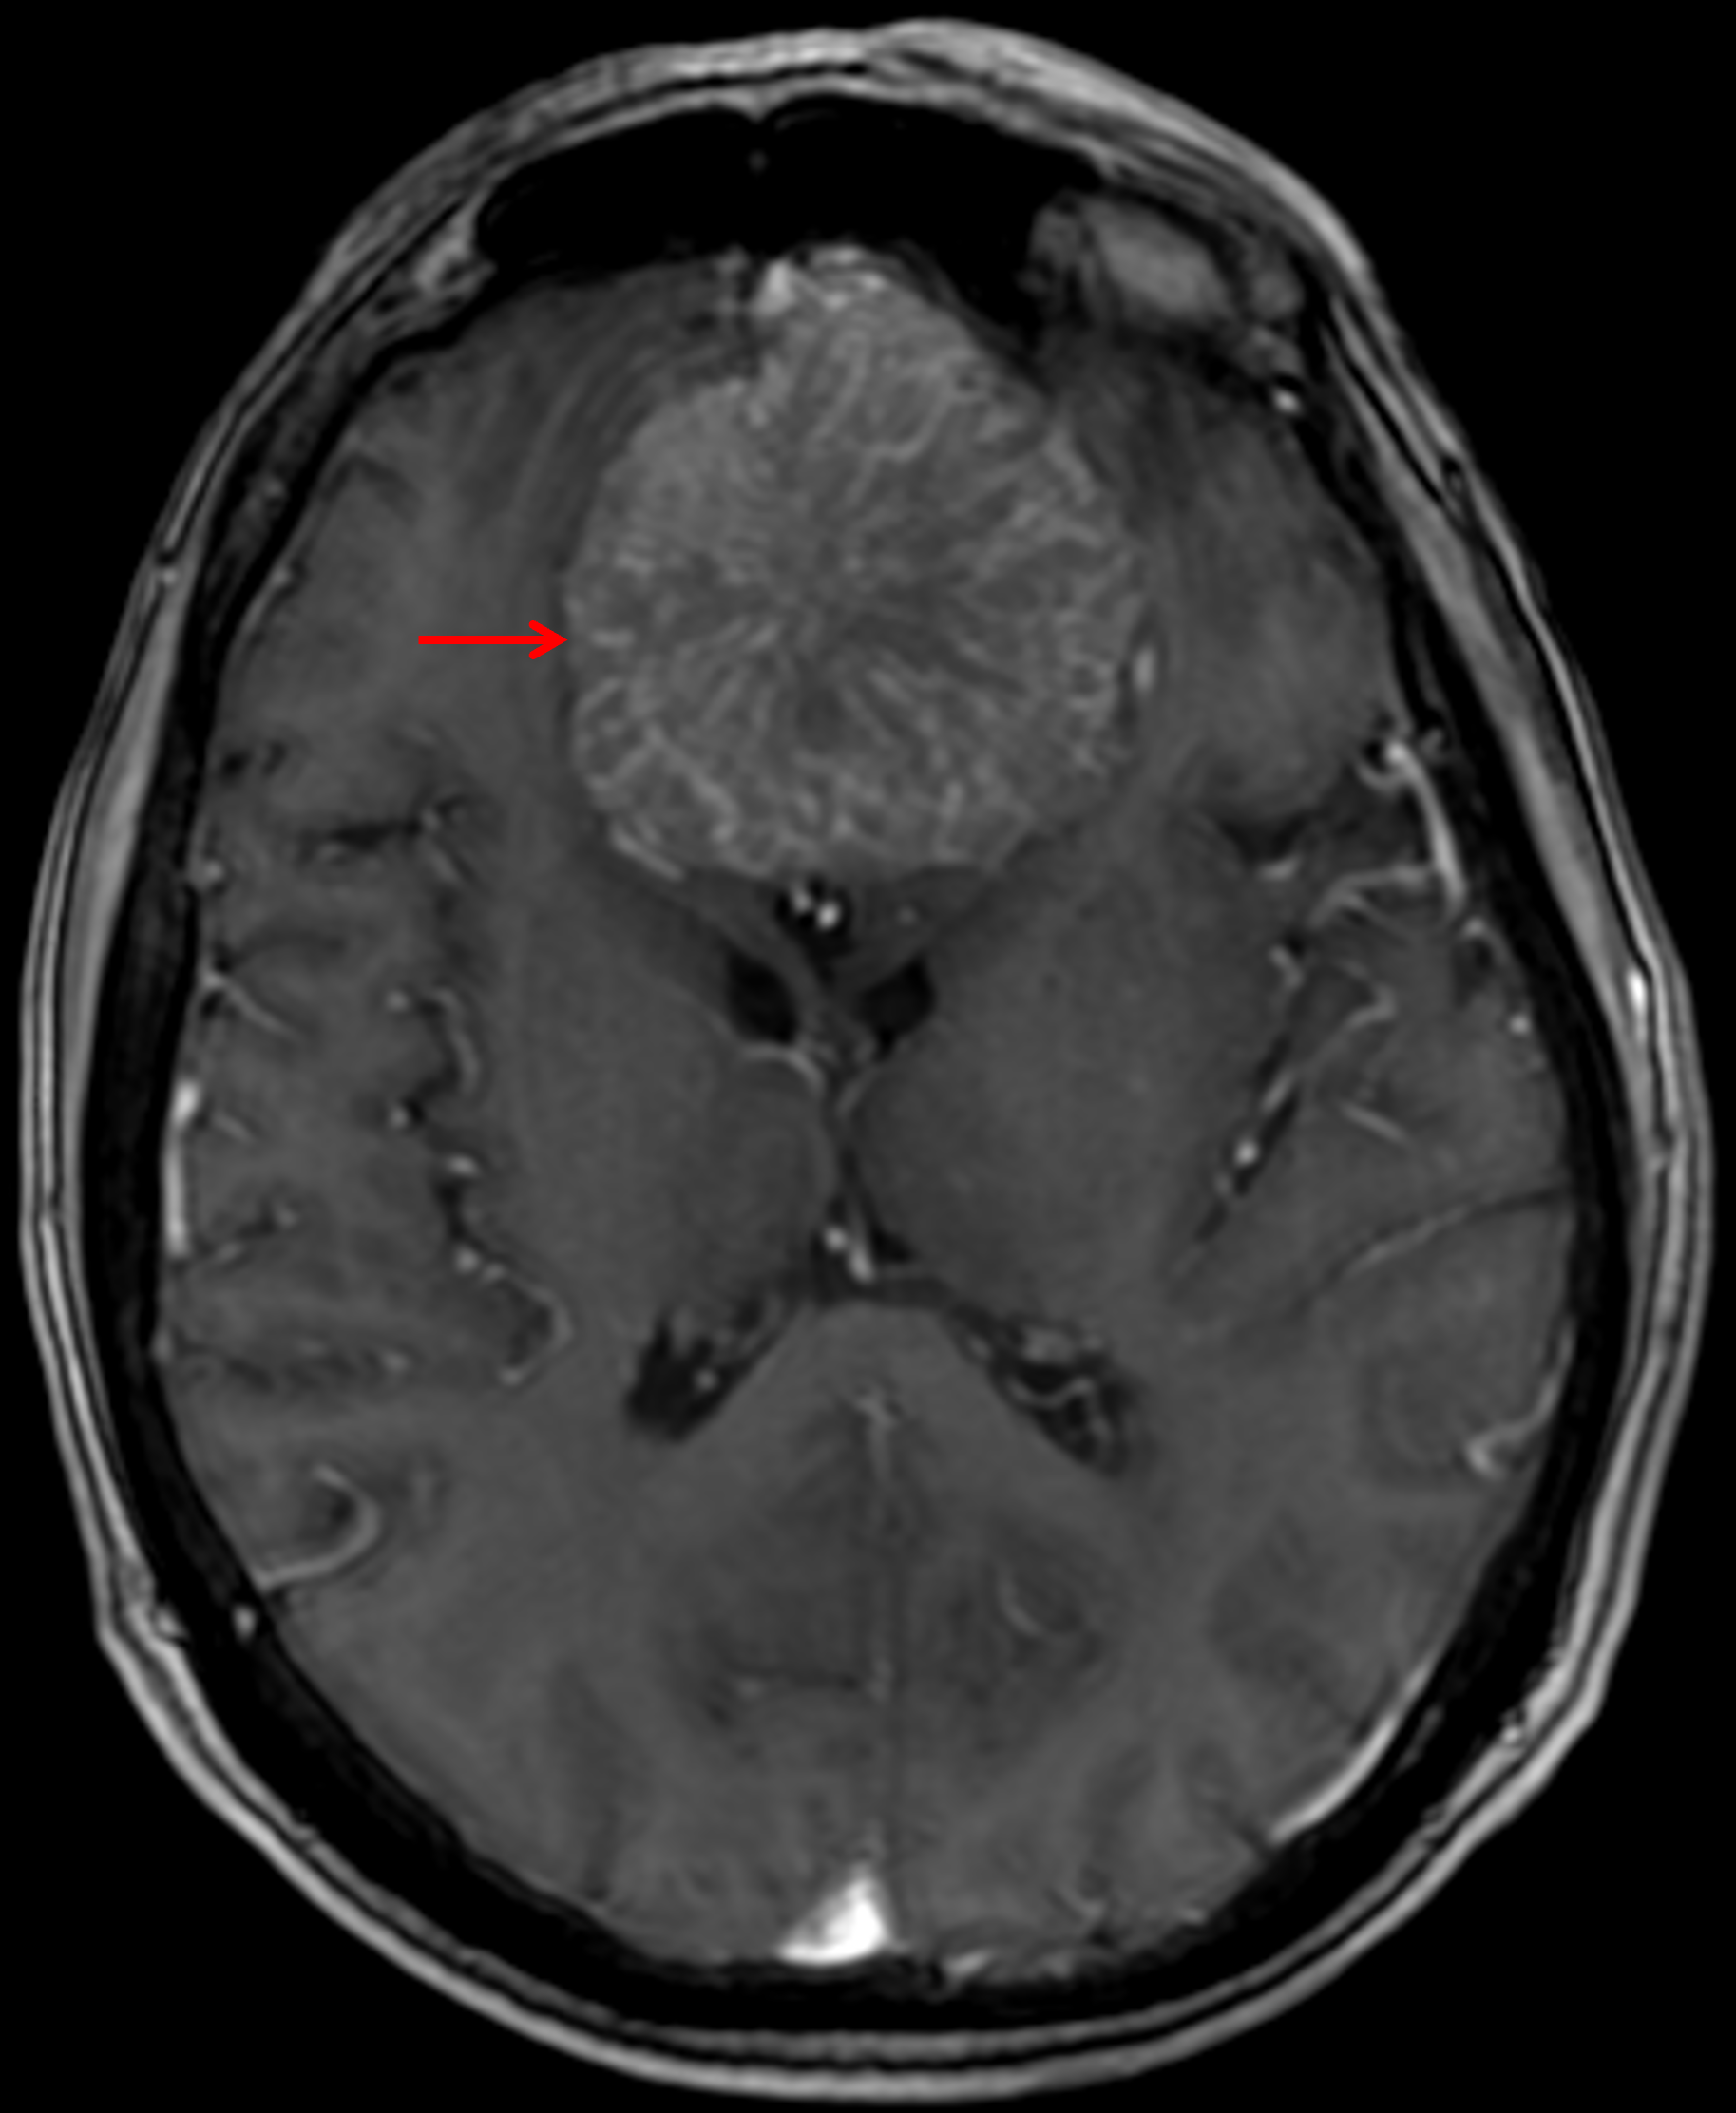

Age: 65

Sex: Female

Indication: Headache

Meningioma